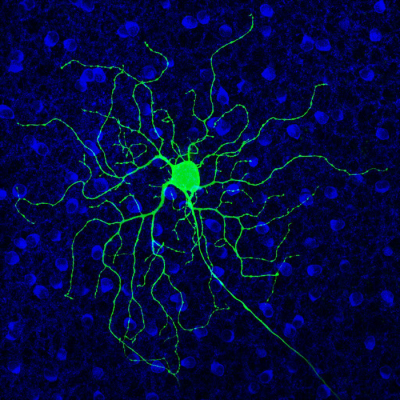

Green retinal ganglion cell spreads dendrites in all directions.

A mouse retinal ganglion cell (green), which becomes hyperactive in degenerative vision disorders. Other retinal cell types are labeled in blue. Image credit: Shubhash Yadav, Kramer lab, University of California, Berkeley.